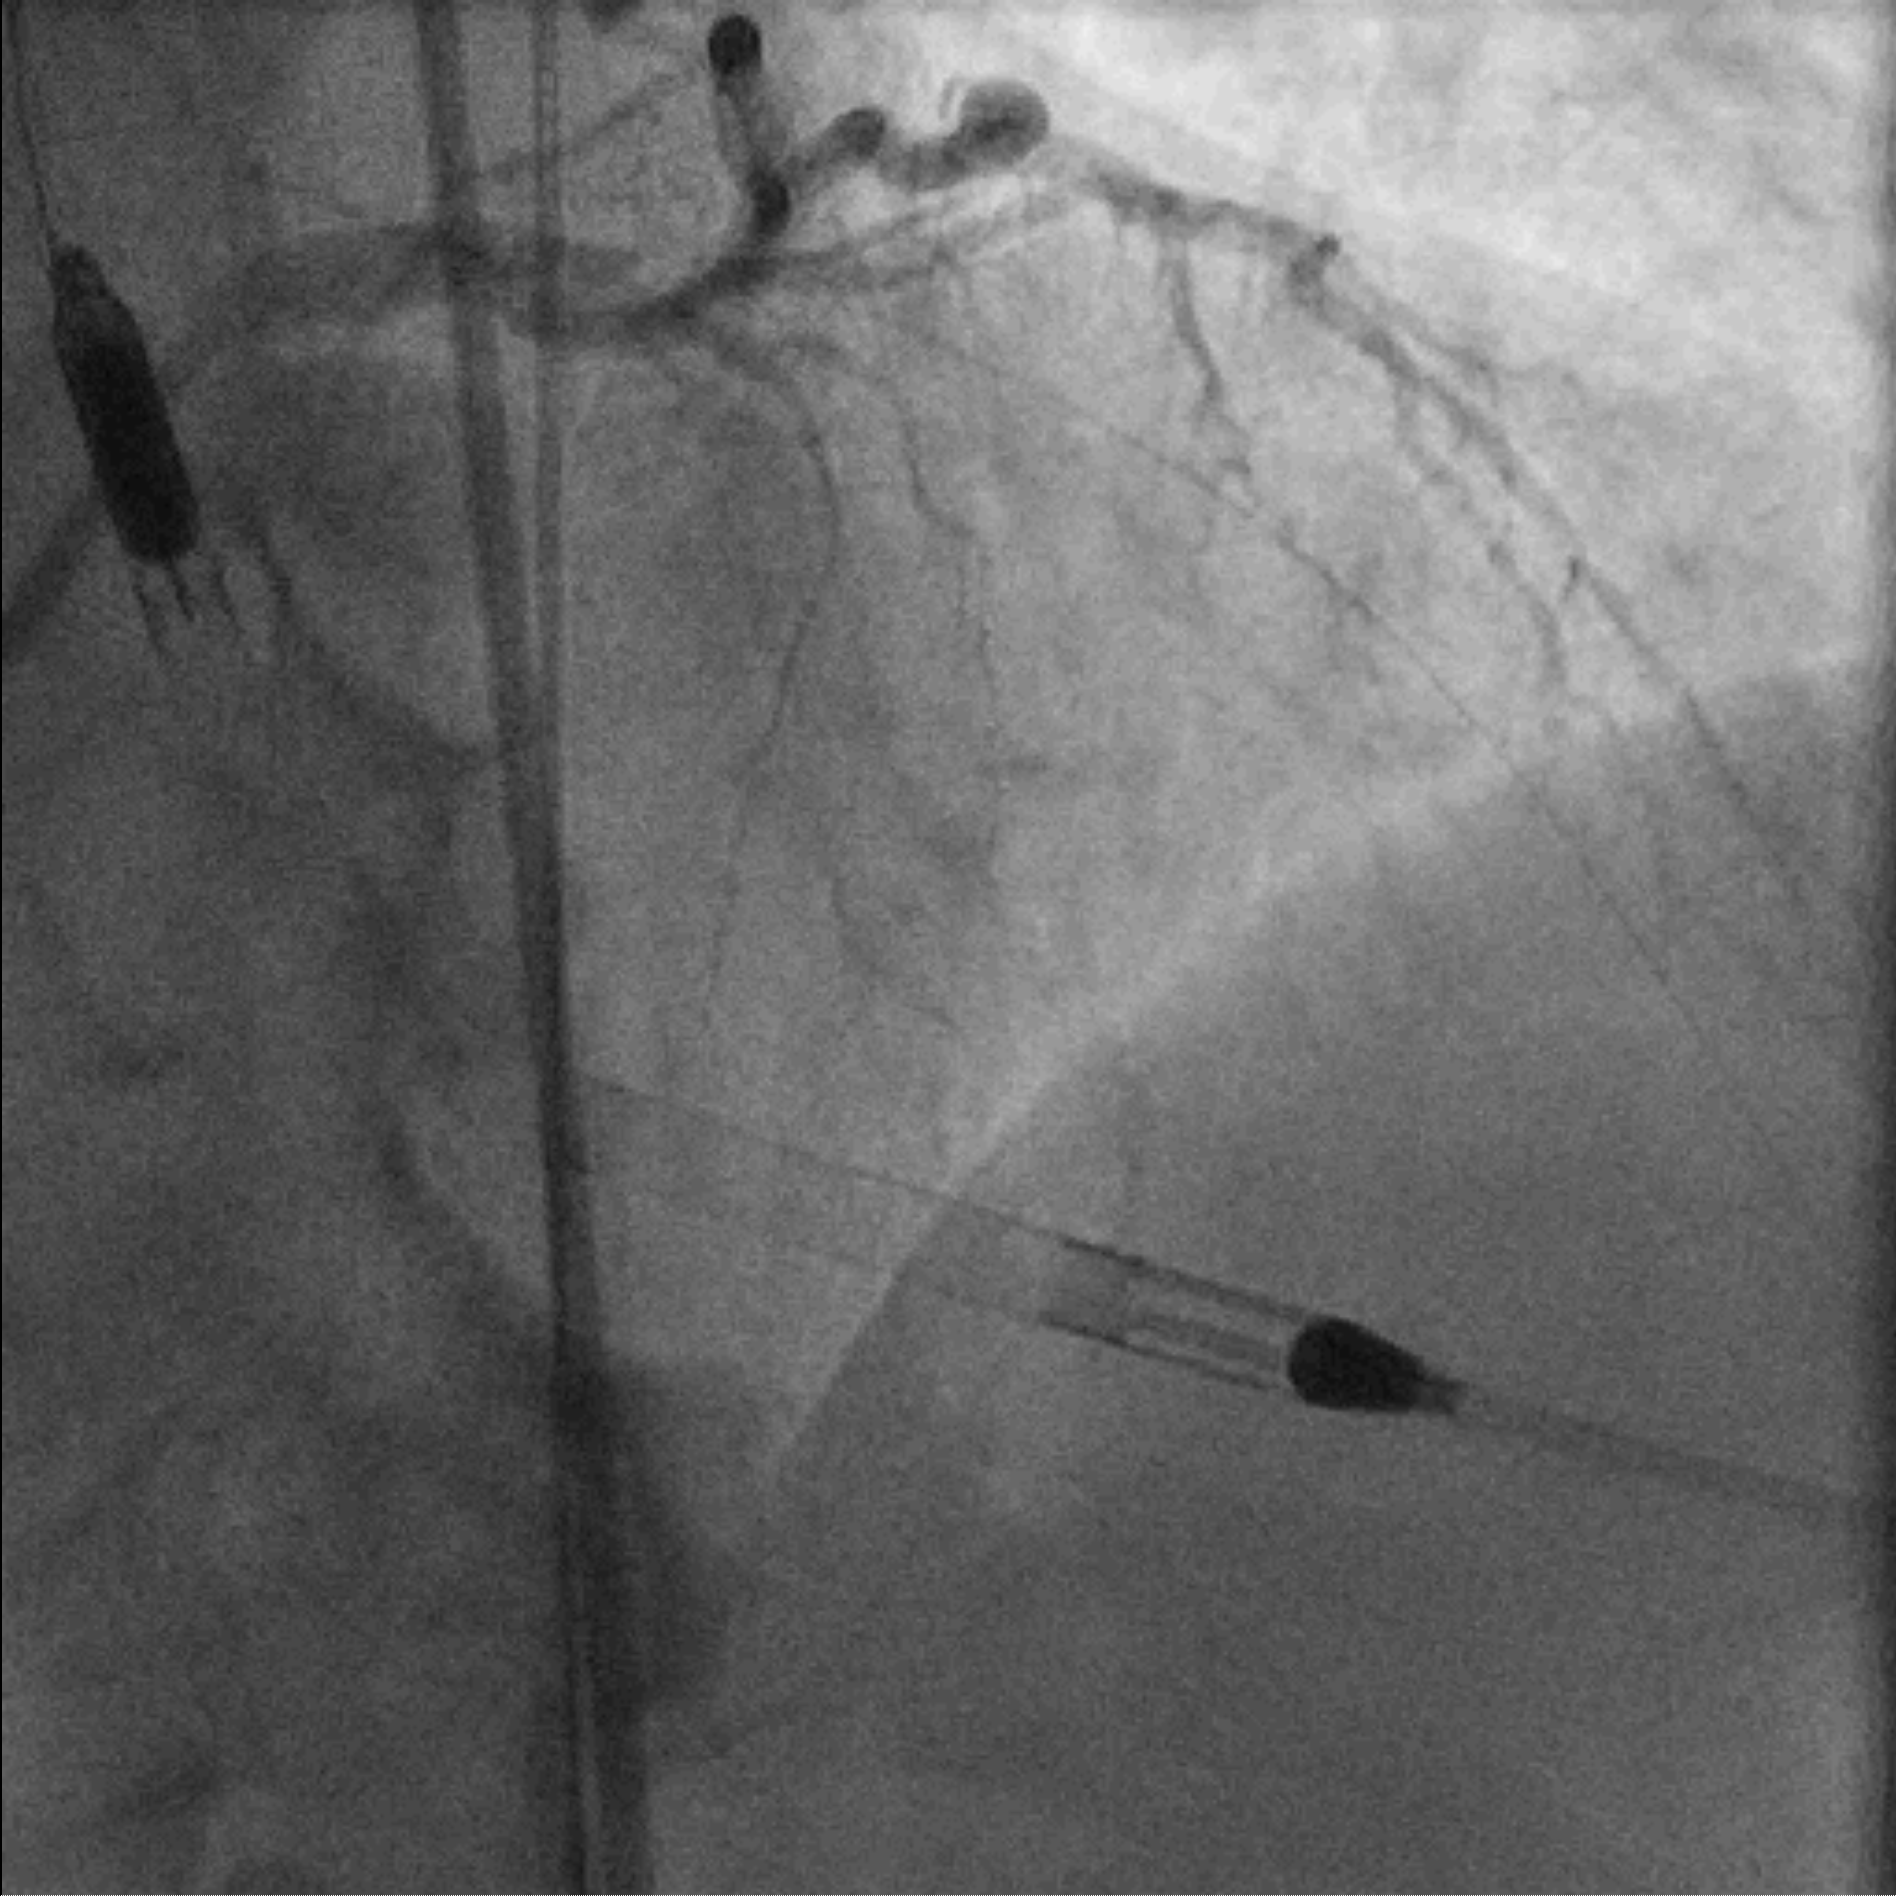

EBU 3.5 7Fr was used to engage left main common artery. Proximal LAD lesion was crossed with a Corsair Pro XS supported Fielder XT-R. Dottering with Sapphire 2.0/15 was unable to achieve flow in LAD. Low pressure inflation of 2.0 mm x 15 mm semi-compliant balloon at ostial to proximal LAD restored TIMI II flow. IVUS demonstrated organised clot in pLAD and plaque extension into LM. A 3.5 mm x 48 mm DES was deployed over mid-LM to mLAD at nominal pressure. The stent was further optimized with 5.0 mm x 6 mm and 4.0 mm x 15 mm non-compliant balloons under IVUS guidance. Intracoronary Adenosine was administered to improve coronary flow. Final angiogram showed TIMI III flow with no immediate complications. Faint retrograde flow to distal RCA was observed. A brief attempt to open RCA was made as the chronicity of the lesion was uncertain. However, Fielder XT-A supported by Corsair Pro XS failed to cross the lesion and the procedure was aborted.